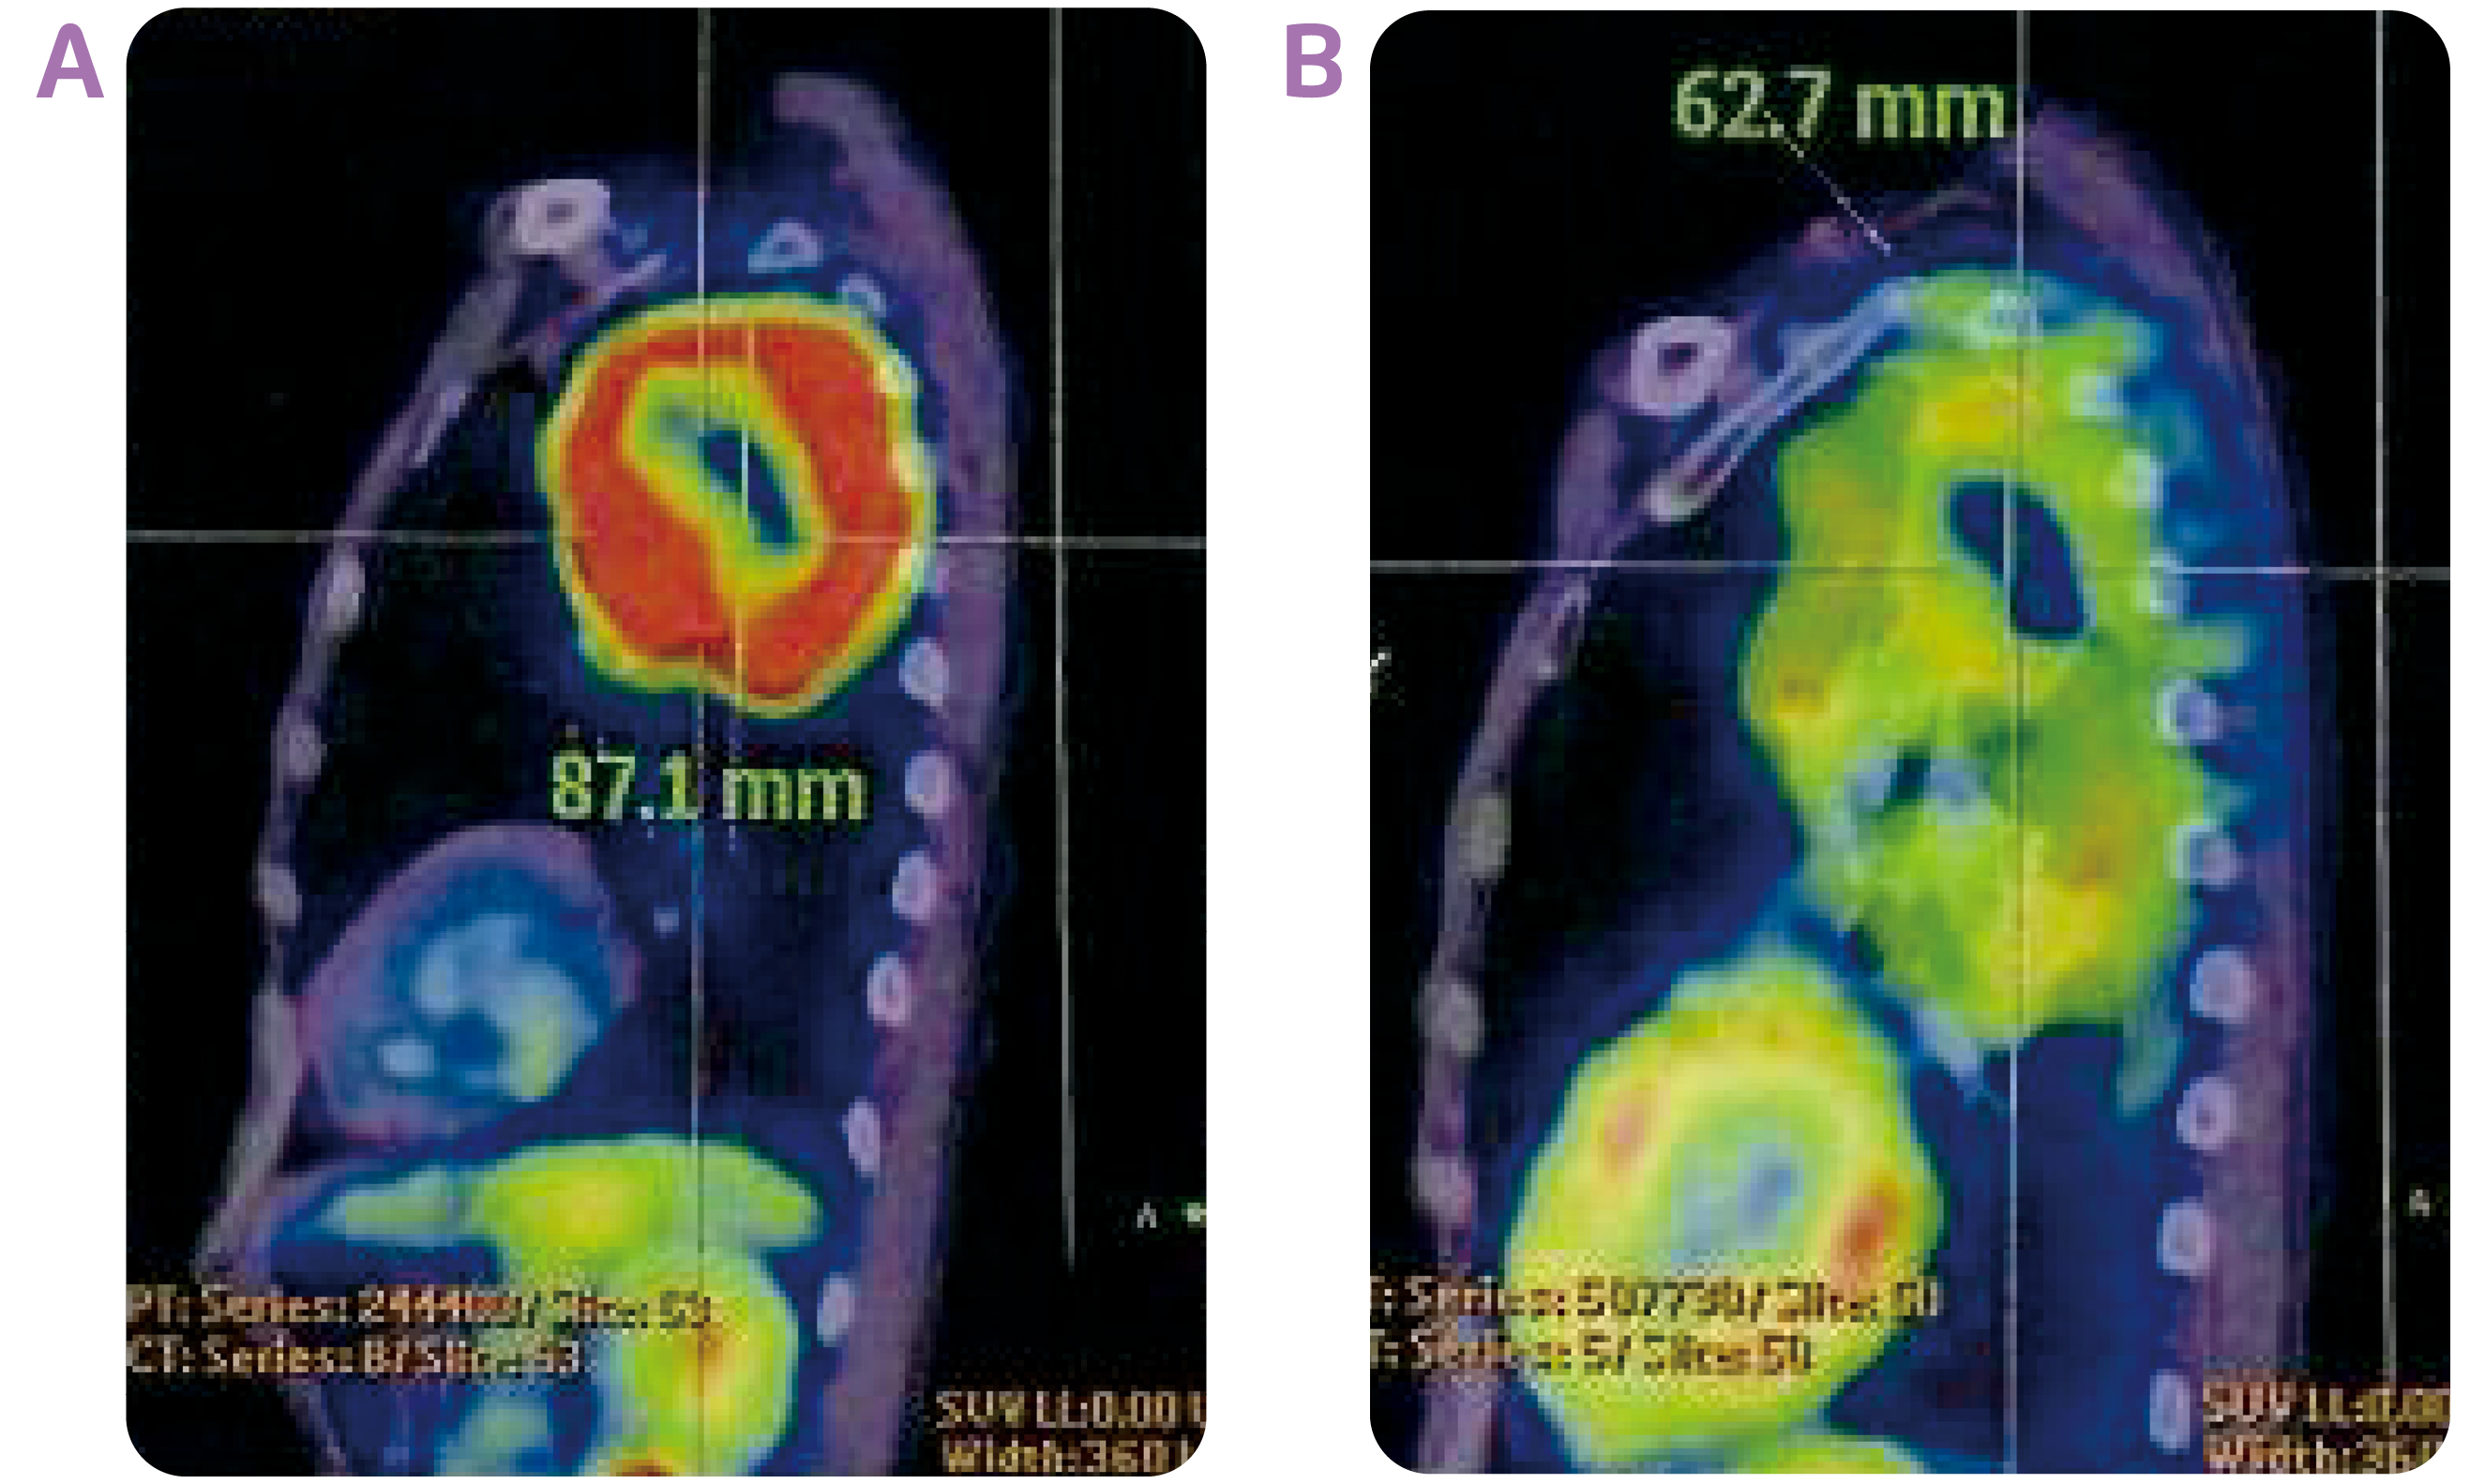

Dr. Choy shared a case of the use of durvalumab consolidation after cCRT in stage III NSCLC. The patient was a 65-year-old construction worker who had smoked a pack a day for 40 years. He was presented with anterior and posterior upper chest wall pain on the left side of his body, which he had experienced for 1 year, and slight shortness of breath. Positron emission tomography-computed tomography (PET-CT) scan of the chest indicated a mass measuring 8.7 cm in diameter in the left upper lobe (Figures 1A and 2A). The tumour had grown into mediastinum, surrounding the aortic arch and descending thoracic aorta. Multiple hypermetabolic lymph nodes were detected. CT-guided biopsy revealed adenocarcinoma. No evidence of distant metastases to the liver, adrenal glands and bones led to a diagnosis of stage IIIB NSCLC (T4N2M0). His serum carcinoembryonic antigen (CEA) level at the time of diagnosis was 143 ng/mL. Molecular profiling revealed the tumour was negative for epidermal growth factor receptor (EGFR) mutation and anaplastic lymphoma kinase (ALK) rearrangement, while the tumour proportion score (TPS) of PD-L1 was 10-20%.

The achievement of partial response with the cCRT, led to the choice of durvalumab consolidation treatment. The patient started receiving durvalumab (10 mg/kg) every 2 weeks at 19 days after completion of cCRT. The tumour continued to shrink with the treatment (Figure 1C), and measured 6.3 cm in diameter after the patient had taken 8 doses of durvalumab (Figure 2B). The consolidation treatment was well-tolerated, and the patient only had a mild rash for the first two months. The patient has now completed the 26 doses of durvalumab, and his serum CEA level has further dropped to 2.9 ng/mL. He is able to be fully committed to his work as a construction worker. “Durvalumab consolidation treatment is highly useful in preventing disease progression in patients with unresectable, stage III NSCLC following cCRT,” concluded Dr. Choy.

Figure 2. The PET-CT images of the tumour site taken (A) at diagnosis and (B) after 8 doses of durvalumab